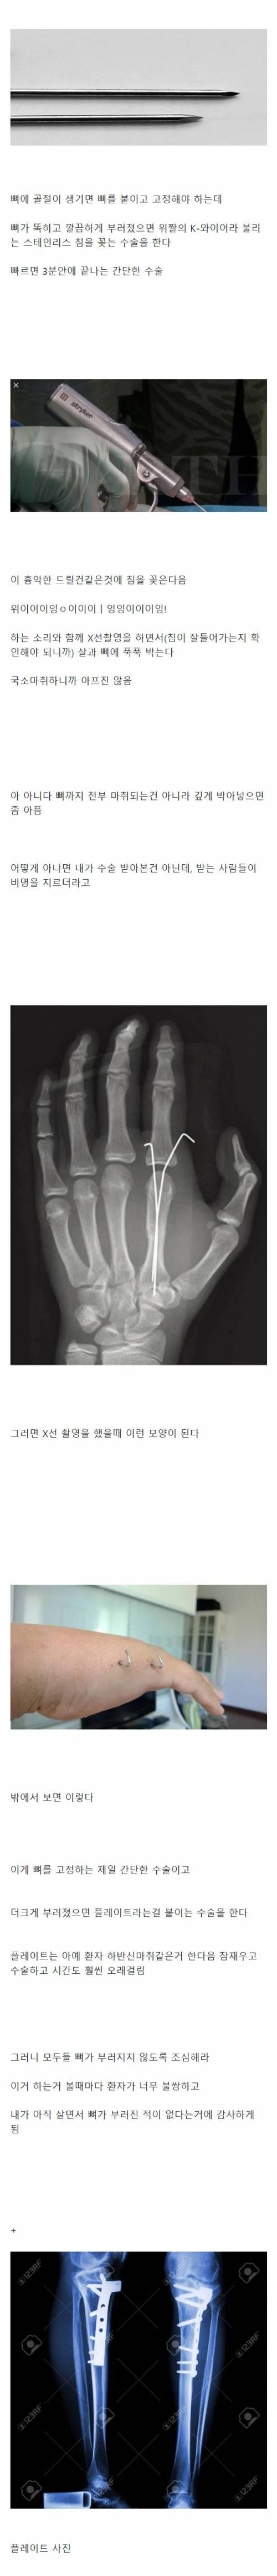

뼈 안뿌러져 본 사람들이 모르는 사실들